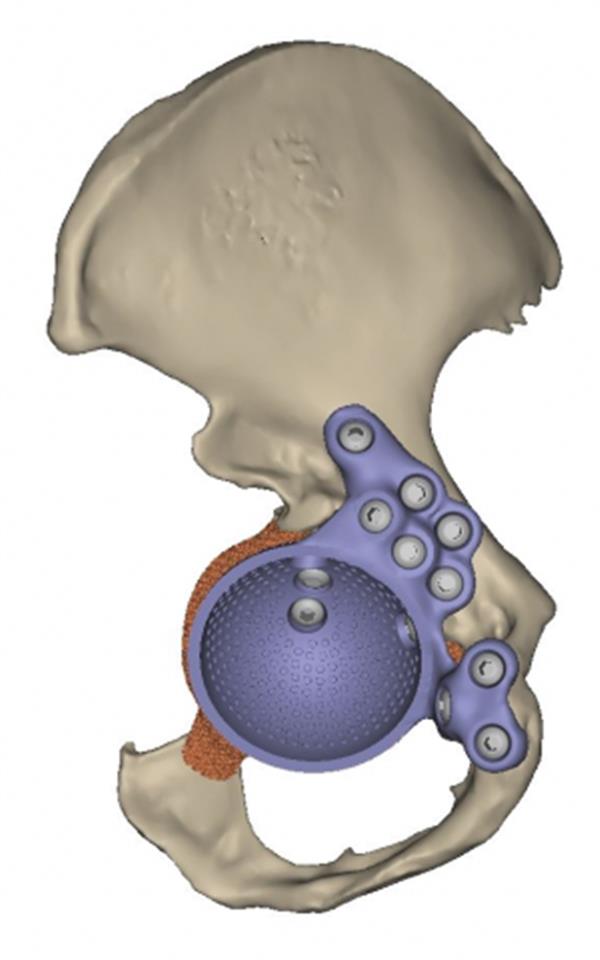

2010年,医生手术切除了Fellesen的神经纤维瘤,但术后几个月出现了股骨折断,她的病情因此恶化。当时,除了在家受教外,Fellesen没有别的选择,此后两年她均无法步入课堂。医生认为Fellesen将要在轮椅上度过余生。 瑞典Lund的Skane大学医院的Rydholm教授的加入是一个新的转折点。2012年,Rydholm教授联系了比利时公司Materialise的子公司Mobelife,据天工社了解,后者专注于医疗3D打印。Mobelife的工程师团队立即投入工作为Fellesen设计一个定制的髋臼植入物。 通过使用Mimics软件,专家导入并分割了Fellesen髋关节的CT扫描来重建受损区域并检查术前情况。借助手术模型,医生能直接根据患者的特殊情况进行术前计划。这个定制化过程包括放置标识点来确定髋臼杯和凸缘的位置并保证它们是在正确的位置上。

Mobelife团队为Fellesen设计了一个与她的臀部结构完全相匹配的定制化植入物。为了此次手术,该团队使用了医疗3D打印软件3-matic,,该软件允许用户直接在三角面上展开工作。他们还为Fellesen设计了一个定制的凸缘,并确定了螺钉的位置。为了支撑螺钉,他们用Mimics里CT数据的灰度值对Fellesen的骨质量进行了分析。 此外,为了确保植入物和骨组合能承受髋关节的多次运动和压力,Mobelife团队进行了一次有限元分析(FEA)。一名外科医生验证了最终的设计,随后该设计被导出并被3D打印。他们用钛合金在一台LayerWise 3D打印机打印出植入物。